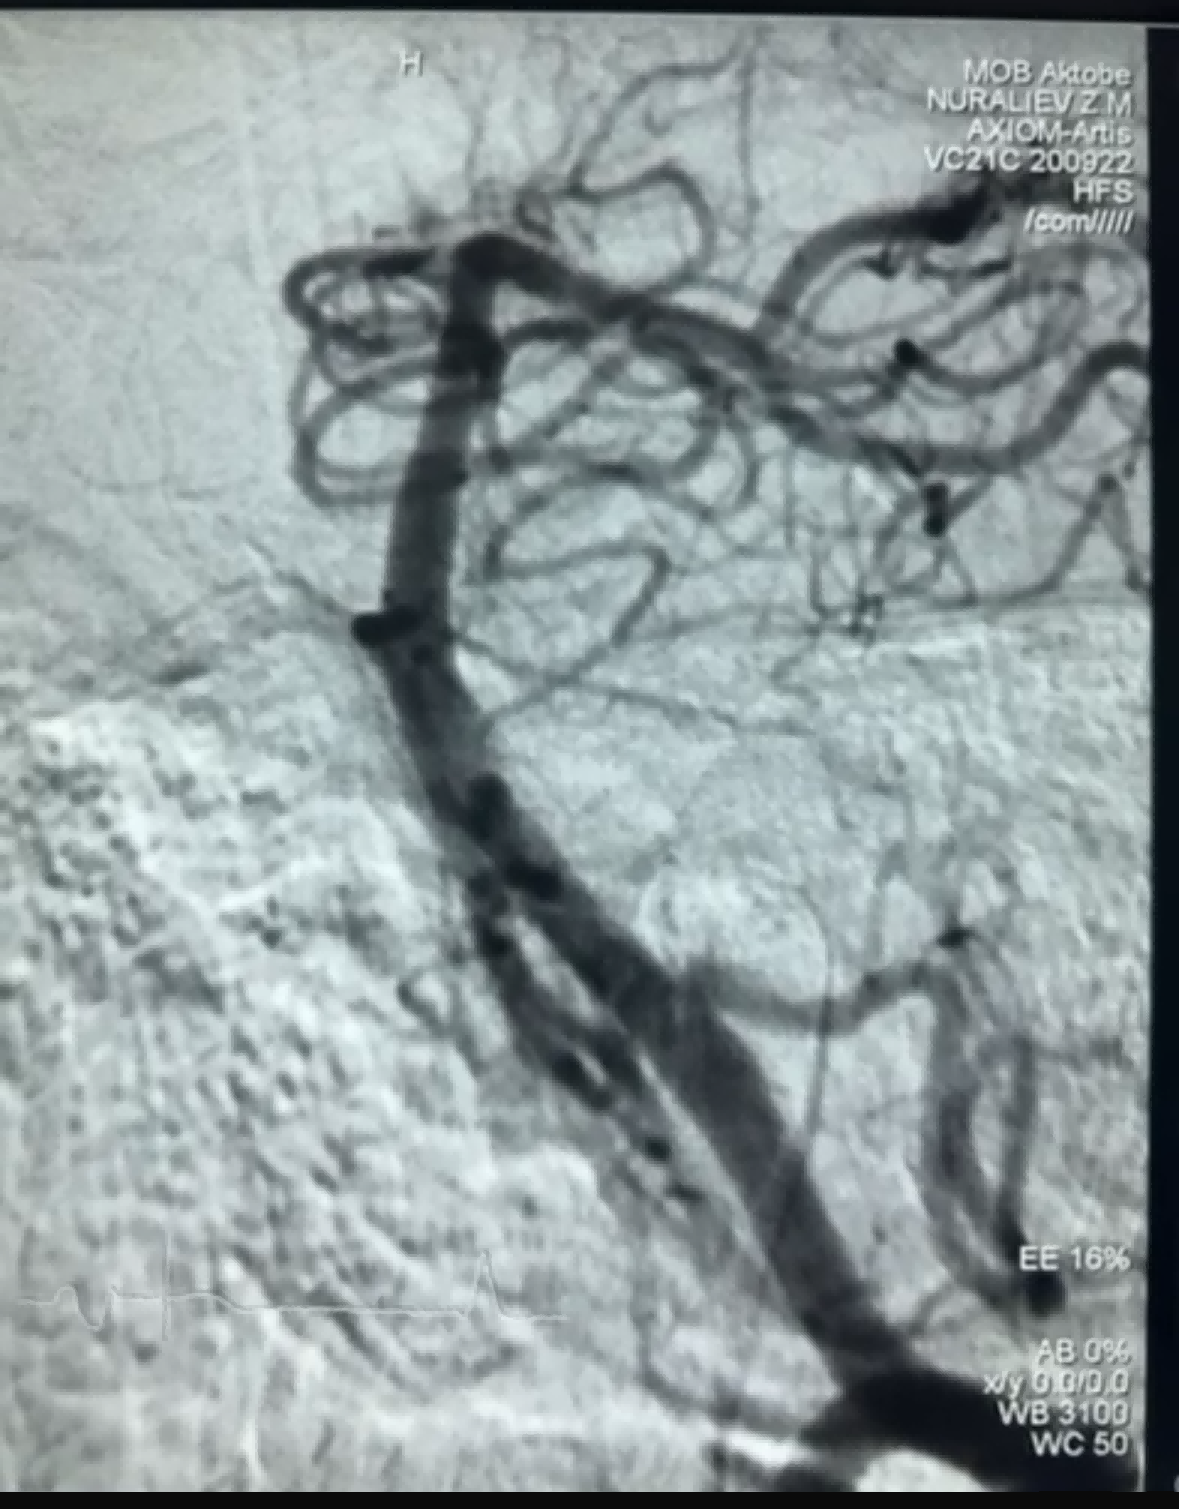

Baru-baru ini, ada kasus trombektomi yang berhasil menggunakan Dredger Stent Retriever dari NeuroSafe Medical Co., Ltd. Dredger Stent Retriever memiliki ujung lembut non-invasif, yang sangat mengurangi risiko kerusakan intima, dan memiliki desain lubang berbentuk khusus yang unik yang menangkap bekuan darah terutama dengan menjepit perubahan celah.